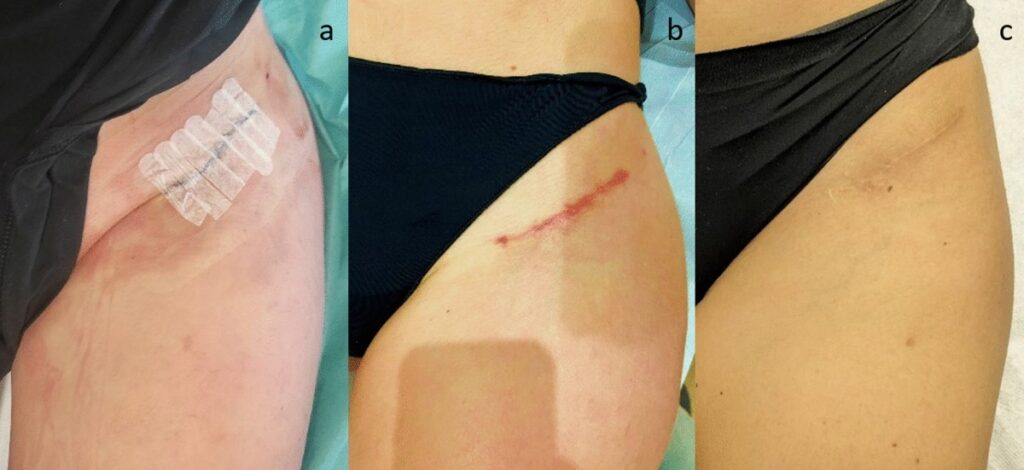

A bikini incision total hip replacement is a form of direct anterior hip replacement surgery where the incision is made in line with the natural skin crease of the groin, similar to where a bikini bottom would sit. This technique aims to reduce visible scarring while maintaining the benefits of the anterior approach, including muscle-sparing access and the potential for faster recovery.

The incision is placed along the natural groin crease, resulting in a scar that is less noticeable, especially when wearing swimwear or underwear. - Muscle-sparing approach

Cosmetic scar management

To support optimal healing of your scar:

- You’ll be given wound care instructions post-surgery

- Scar massage and moisturisation may be recommended at the appropriate time

- Avoiding sun exposure to the healing scar helps reduce pigmentation

- You may discuss the use of silicone dressings or creams with your surgeon if desired

While all surgical scars fade over time, the placement of the bikini incision helps keep the scar discreet and more easily concealed.